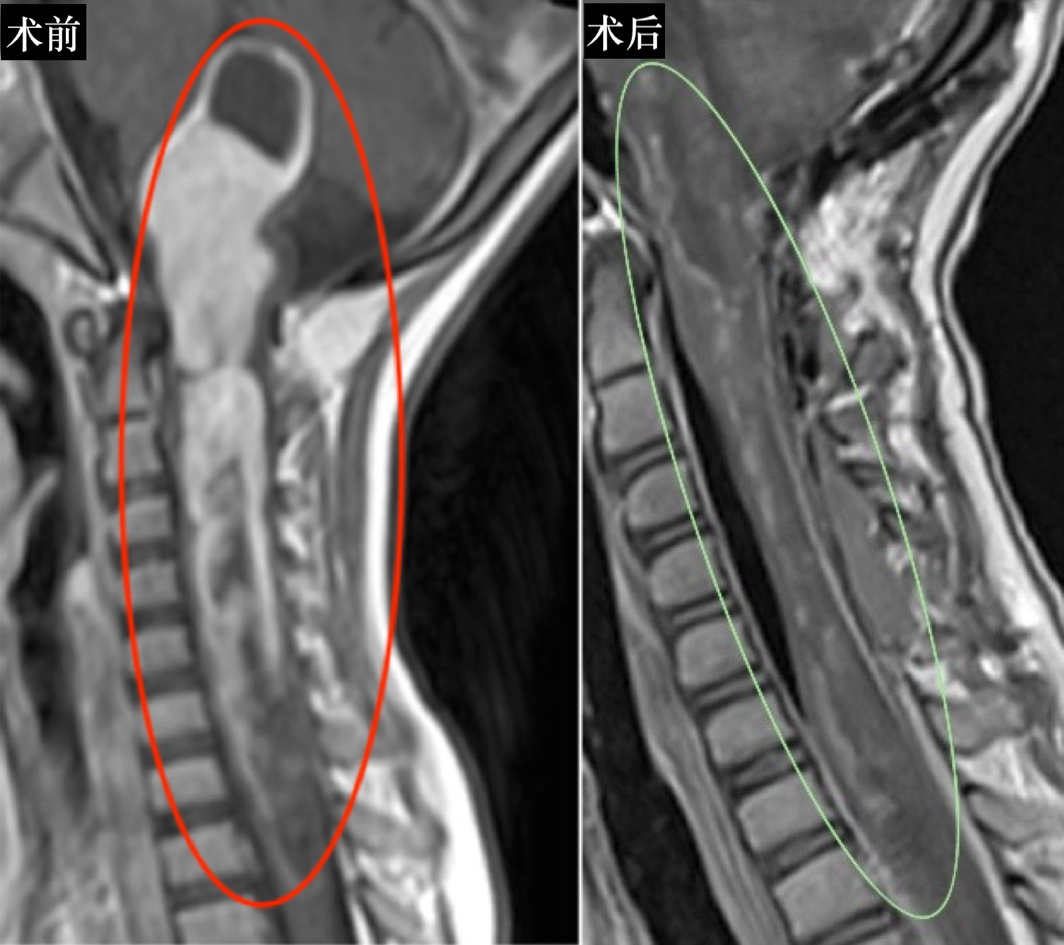

结果显示:脑干延髓和第四脑室至胸髓T3水平存在囊性肿瘤。神经系统检查显示水平性眼球震颤、重度左侧偏瘫和同侧反射活跃。

术中监测和运动诱发电位始终保持稳定。巴教授确认显微镜下达到满意切除程度后,决定进行术中磁共振(iMRI)扫描检查,以明确肿瘤是否完全切除。

然而术中MRI检查结果显示,右侧C1-C2水平仍有少量肿瘤残留。手术继续实施,巴教授对这些区域残余肿瘤再次切除。术中MR检查后证实病变已完全切除。最后为确保患儿术后正常行动能力,巴教授还实施颅骨成形术及椎板原位复位术。

术后结果:神经功能显著改善

术后,亿亿无神经功能损伤,术前吞咽困难症状改善,左侧运动功能障碍得到改善。术后组织病理学诊断为间变性星形细胞瘤。